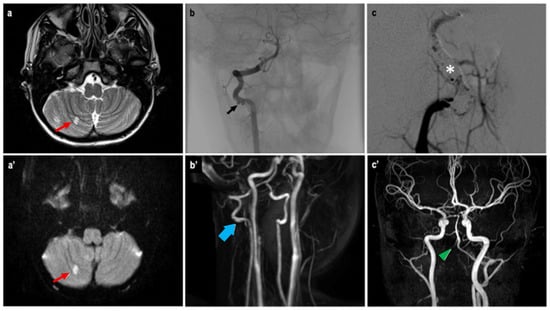

3. Case Report

| Our case report | 2025 | Italy | 1 | 14 | M | Occipital condyle | Headache, dizziness, impaired vision, and fall | No | No | Resection | 1 yr |